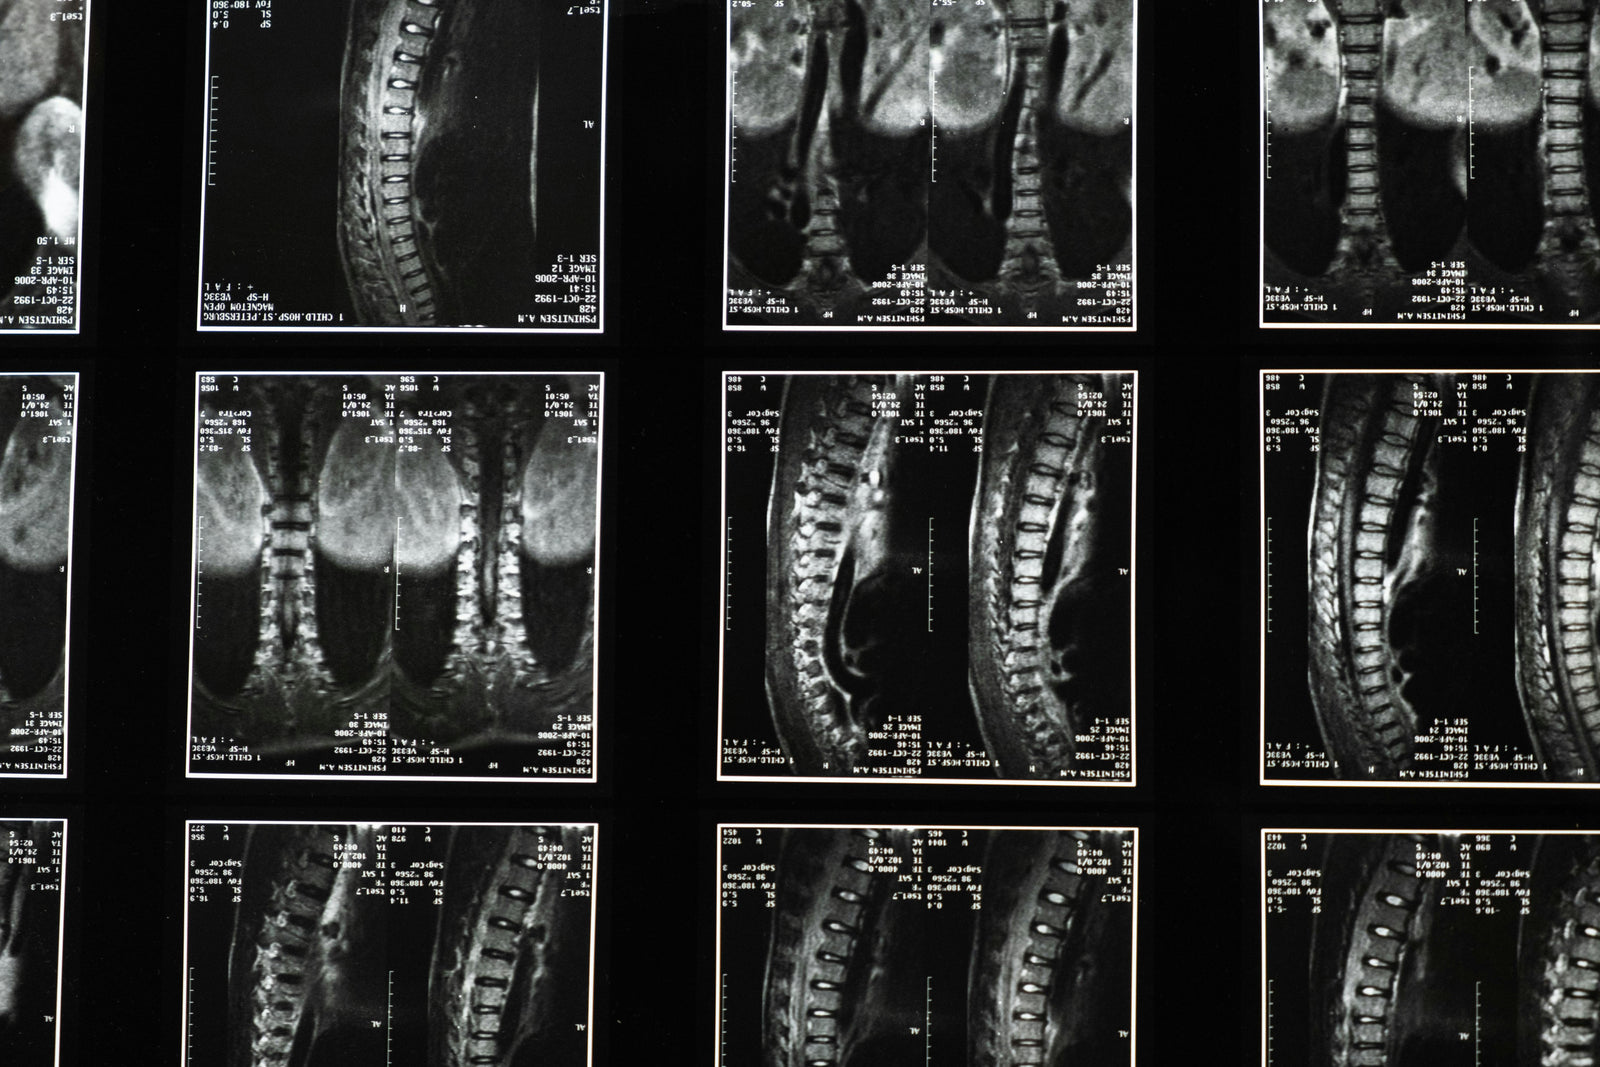

Magnetröntgen används för att undersöka ryggradens kotor, diskar, nerver och mjukdelar med hög detaljrikedom. Det är särskilt relevant vid långvarig ryggsmärta, utstrålning i ben eller armar, domningar eller när andra undersökningar inte gett tillräckliga svar.

MR kan bland annat hjälpa till att bedöma diskbråck, nervpåverkan, spinal stenos, inflammation, stressreaktioner och andra förändringar i ryggraden.

Undersökningen kan visa diskbråck, nervrotspåverkan, spinal stenos, kotförändringar, inflammation och mjukdelsskador med hög detaljrikedom.